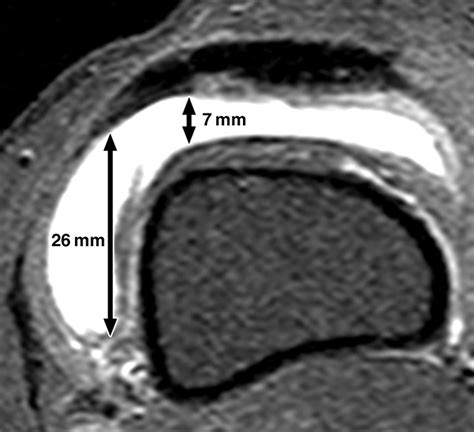

At its core, a small knee effusion is an accumulation of synovial fluid. Synovial fluid is a natural lubricant that keeps your knee moving smoothly. However, when the joint is irritated—due to trauma, overuse, or disease—the body produces more of this fluid than it can reabsorb. This creates a subtle swelling that you might notice as a slight tightness when bending the knee or a puffy appearance around the kneecap.

Unlike a massive effusion that restricts movement significantly, a minor case might be barely noticeable. You might still be able to walk, but you may experience a dull ache or a sensation of fullness. It is critical not to ignore these symptoms, as even a small knee effusion can serve as an early warning sign of deeper joint issues that could worsen if left untreated.